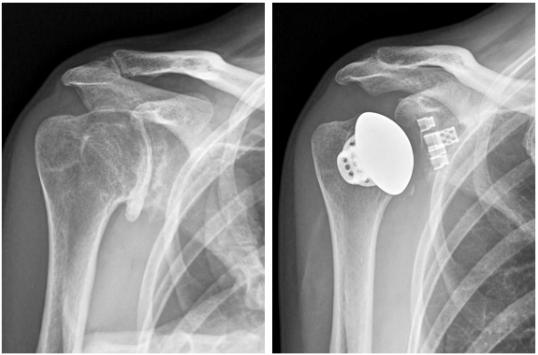

作为该公司四肢产品线的最新成员,2018年无茎肩关节是一种用于解剖全肩关节置换的保骨假体。该公司表示,该装置由一个无茎笼、一个肱骨头和一个笼和骨盆组成,在手术中是灵活保持骨骼的理想方法。此外,为了提高生物固定的可能性,它被纳入一个3d激光打印多孔骨笼结构,使骨头通过骨骼生长,不需要一个茎,从而使植入更容易,减少手术时间和减少失血。精确技术指出,三维多孔材料与骨笼技术的结合使其在市场上脱颖而出。

目前,微创骨科手术是外科手术的主要趋势,如无茎肩部植入,主要由德国和法国专家领导。美国外科医生也注意到使用无茎植入物进行关节置换的好处,这种植入物的骨丢失和并发症比传统的解剖肩关节假体少。

作为创新的植入物、仪器和计算机辅助节肢动物手术技术的开发者和生产者,techech的目标是在释放后立即评估无茎肩关节,并积极扩大和升级其产品。和其他无茎植入物制造商一样,这里的目标是尝试重建原来的肩部解剖和尽量减少肱骨移植。